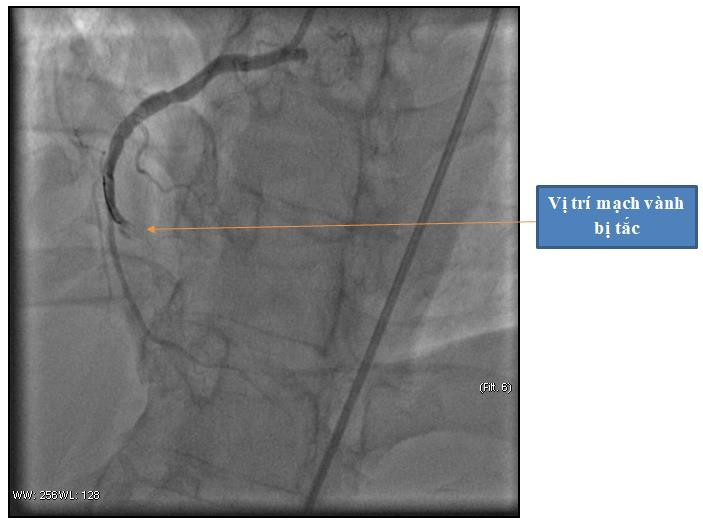

Hình ảnh động mạch vành phải bị tắc hoàn toàn - Ảnh BVCC

Kết quả thăm khám cho thấy người bệnh bị nhồi máu cơ tim cấp trên nền tăng huyết áp và nhanh chóng được chuyển lên Khoa Can thiệp tim mạch thực hiện can thiệp cấp cứu.

Tại phòng can thiệp các bác sĩ đã tiến hành Chụp động mạch vành cho kết quả: động mạch vành phải bị tắc hoàn toàn. Do thời gian ngừng tuần hoàn quá dài, người bệnh rơi vào tình trạng suy đa tạng, tình trạng sốc tim và rối loạn nhịp tim vẫn còn. Sau can thiệp, người bệnh được chuyển về Khoa Hồi sức tích cực – Chống độc để điều trị hồi sức chuyên sâu.